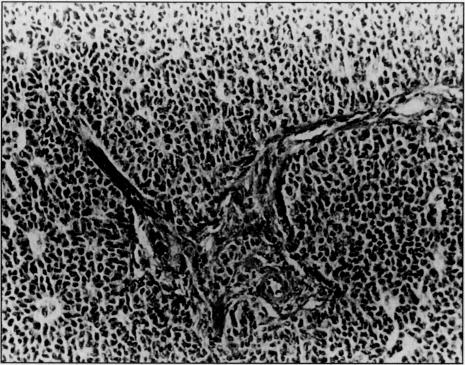

As the number of postmenopausal women increases, physicians will have more opportunities to treat elderly women with gynecological complications. This case report describes a 76-year-old, obese, multiparous woman, known to have gallstones who presented with acute abdomen complaints and was admitted for observation. Treatment was delayed until significant blood loss was recognized. At laparotomy, a ruptured ovarian granulosa cell tumor was found.

随着绝经后女性数量的增加,医生将有更多机会治疗患有妇科并发症的老年女性。本病例报告描述了一名76岁、肥胖、多产的女性,已知患有胆结石,因急性腹痛症状就诊并入院观察。治疗延迟至发现有明显失血情况。剖腹手术时,发现一个破裂的卵巢颗粒细胞瘤。